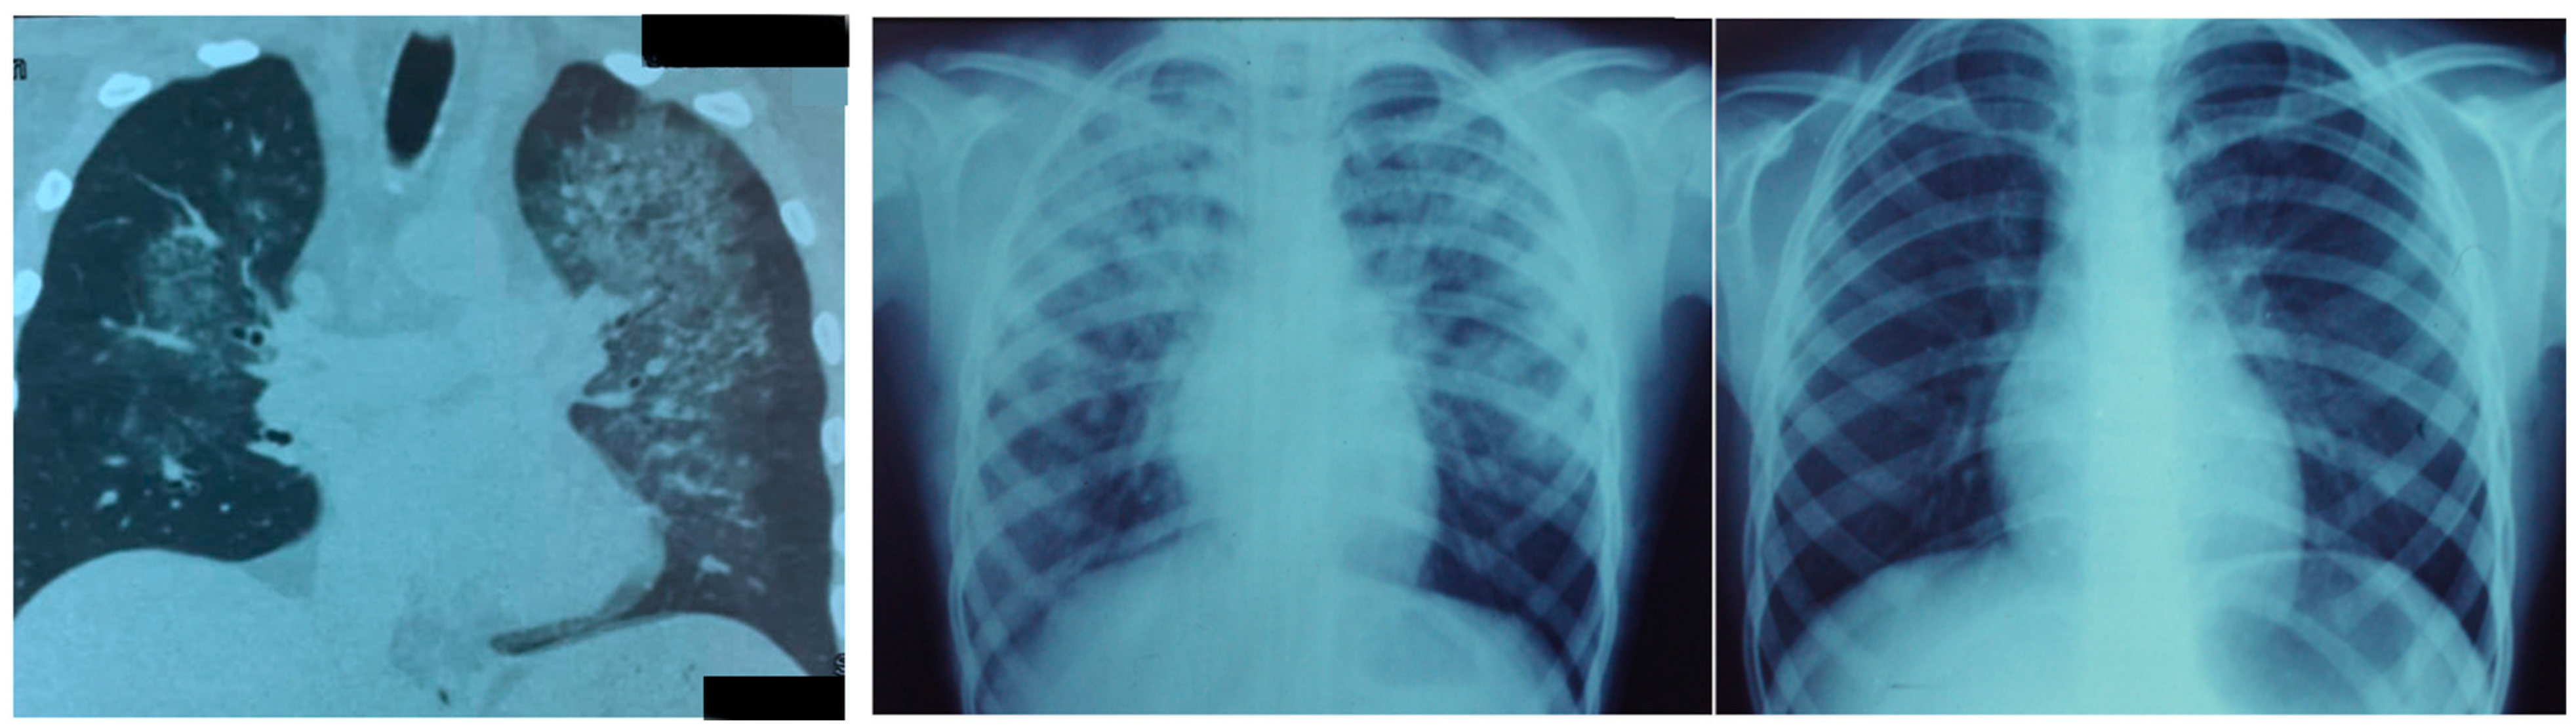

This “new” pathology differs from high-altitude pulmonary edema (HAPE), which occurs during rapid ascent to high altitude in some individuals (Figure 2).

Figure 2.

High-altitude pulmonary edema. (Left) Chest CT scan, where a patchy, irregular distribution of edema is shown in both lung areas. (Middle) X-rays showing a full blown HAPE. (Right) Results 48 h after, showing full clearance of edema from both lungs.

Morphological (histopathological and radiological) and functional findings of COVID-19 and acute interstitial pneumonia, acute respiratory distress syndrome (ARDS), and high-altitude pulmonary edema (HAPE) share common clinical traits but have peculiar pathophysiological features [26]. HAPE patients can present for consultation with a PaO2 as low as 30 mmHg, even walking in from the city of La Paz (3500 m) (Figure 3). Appropriate treatment leads to complete resolution and reabsorption of lung edema, typically within 2 days in children and sometimes lasting several days in adults [27]. In pneumolysis, lung pneumocytes are destroyed, followed by inflammation, HAPE-type edema, and minor hemorrhage, resulting in severe lung damage, as diagrammatically depicted in Figure 4. HAPE-type edema may be present.